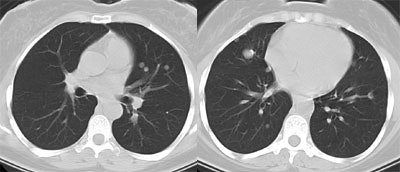

Recurrent Hurthle cell carcinoma: The patient had a history of Hurthle cell carcinoma of the thyroid. Pulmonary metastases are significantly more evident on the coincidence FDG PET examination (below left black arrows) when compared to the I131 scan (below right blue arrows). A CT scan confirmed the presence of pulmonary metastases (below). Note that a subtle bone metastasis to the high left parietal bone can be seen on I131 images. The FDG PET exam did not include this region. |